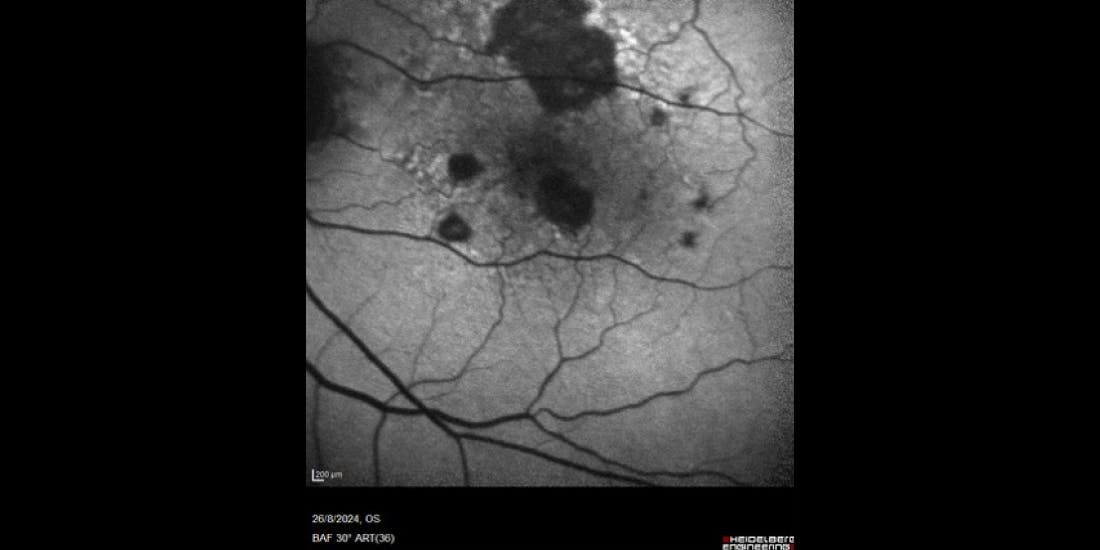

• FAF showed progression of areas of atrophy compared to the prior visit (Figure 4).

• Enlargement of the atrophy was mostly away from the fovea.

<p>Figure 4. Fundus autofluorescence of the left eye of the patient in August 2024. Note the enlargement of atrophic areas compared to the prior visit (shown in Figure 3), largely due to coalescing of lesions.</p>

Figure 4. Fundus autofluorescence of the left eye of the patient in August 2024. Note the enlargement of atrophic areas compared to the prior visit (shown in Figure 3), largely due to coalescing of lesions.